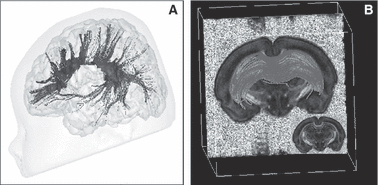

Significant human brain growth occurs during the third trimester, with a doubling of whole brain volume and a fourfold increase of cortical gray matter volume. This is also the time period during which cortical folding and gyrification take place. Conditions such as intrauterine growth restriction, prematurity and cerebral white matter injury have been shown to affect brain growth including specific structures such as the hippocampus, with subsequent potentially permanent functional consequences. The use of 3D magnetic resonance imaging (MRI) and dedicated postprocessing tools to measure brain tissue volumes (cerebral cortical gray matter, white matter), surface and sulcation index can elucidate phenotypes associated with early behavior development. The use of diffusion tensor imaging can further help in assessing microstructural changes within the cerebral white matter and the establishment of brain connectivity. Finally, the use of functional MRI and resting-state functional MRI connectivity allows exploration of the impact of adverse conditions on functional brain connectivity in vivo. Results from studies using these methods have for the first time illustrated the structural impact of antenatal conditions and neonatal intensive care on the functional brain deficits observed after premature birth. In order to study the pathophysiology of these adverse conditions, MRI has also been used in conjunction with histology in animal models of injury in the immature brain. Understanding the histological substrate of brain injury seen on MRI provides new insights into the immature brain, mechanisms of injury and their imaging phenotype.